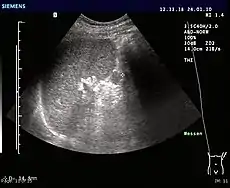

Ultrasonography of an accessory spleen.

An accessory spleen is a small nodule of splenic tissue found apart from the main body of the spleen. Accessory spleens are found in approximately 10 percent of the population[1] and are typically around 1 centimetre in diameter. They may resemble a lymph node or a small spleen. They form either by the result of developmental anomalies or trauma.[2] They are medically significant in that they may result in interpretation errors in diagnostic imaging[2] or continued symptoms after therapeutic splenectomy.[1] Polysplenia is the presence of multiple accessory spleens rather than one normal spleen.

Accessory spleens may be formed during embryonic development when some of the cells from the developing spleen are deposited along the path from the midline, where the spleen forms, over to its final location on the left side of the abdomen by the 9th–11th ribs. The most common locations for accessory spleens are the hilum of the spleen and adjacent to the tail of the pancreas. They may be found anywhere along the splenic vessels, in the gastrosplenic ligament, the splenorenal ligament, the walls of the stomach or intestines,[3][4] the pancreatic tail,[5][6] the greater omentum,[7][8] the mesentery,[9] the renal fossa,[10][11] or the gonads and their path of descent.[12] The typical size is approximately 1 centimeter, but sizes ranging from a few millimeters up to 2–3 centimeters are not uncommon.[2]